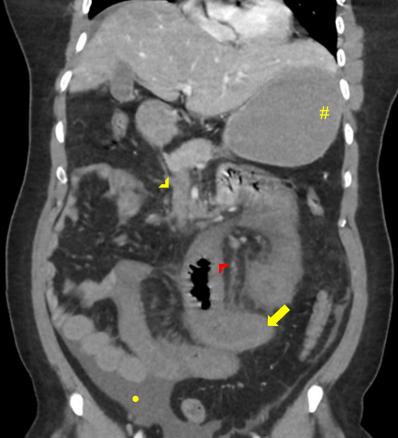

Pointe jaune : thrombose de la veine mésentérique supérieure ;

pointe rouge : hypoperfusion de la paroi grêlique ;

flèche jaune : épaississement de la paroi du grêle ;

point jaune : ascite.